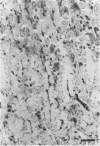

The bacterial genus Helicobacter contains a number of species which colonize the gastric mucosa of mammals. Natural and/or experimental gastric pathology has been correlated with colonization in humans and a wide variety of animal species. Historical reports in the literature suggest that a high percentage of cats are colonized by large, spiral, gastric helicobacter-like organisms (GHLOs). One of these bacteria (Helicobacter felis) has been isolated on artificial media and has experimentally caused gastritis in gnotobiotic dogs. This study surveyed the prevalence of helicobacter colonization in random-source cats by using the urease assay. Histologic examination was performed to determine the degree of associated pathology present. GHLOs associated with chronic gastritis were present in 70% of the juvenile and 97% of the adult cats studied. Although further study is needed to determine specifically what role GHLOs play in feline gastrointestinal disease, these results indicate that helicobacter colonization should be considered in the pathogenesis of feline gastroenteropathy. Furthermore, the high prevalence of feline infection is interesting because cats have recently been implicated as a potential reservoir for human infection by helicobacter-like organisms.